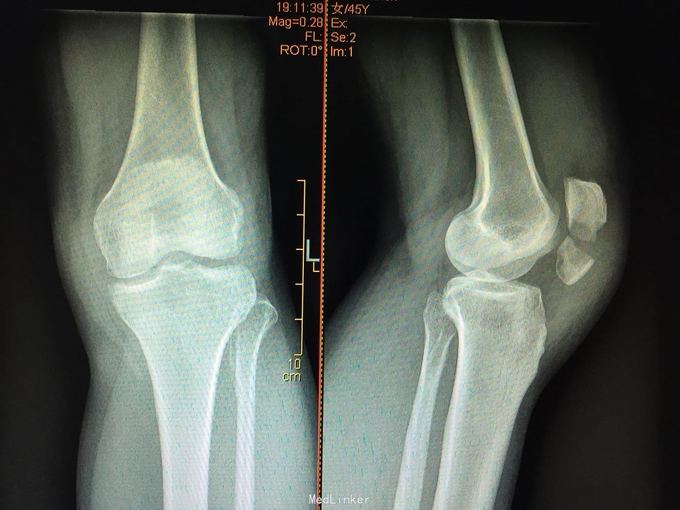

髌骨骨折切开复位克氏针张力带内固定

摔伤致左膝部肿痛活动受限2小时。 46岁女性,行走时不摔摔伤,左膝跪地

左髌骨骨折 急诊行切开复位克氏针张力带内固定术